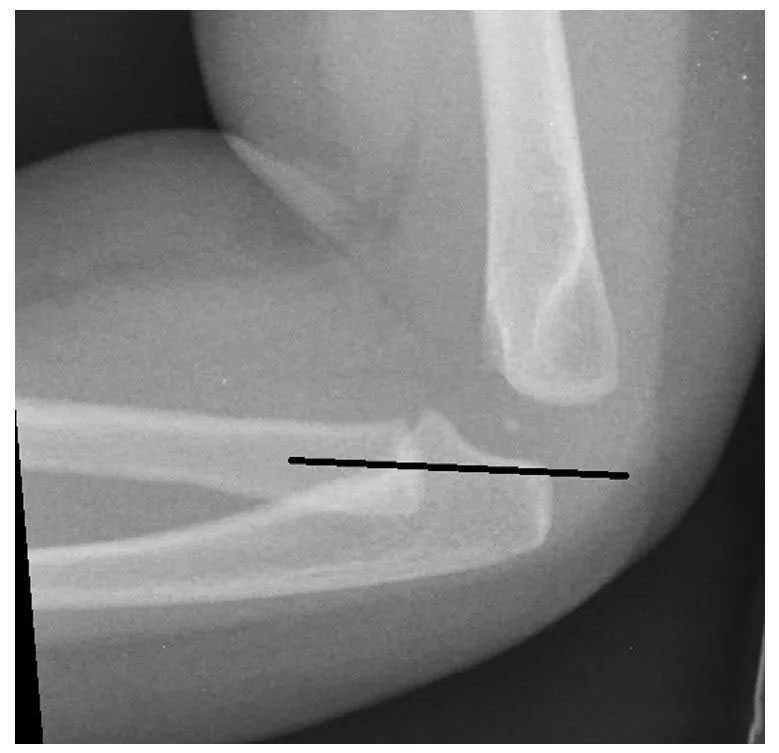

桡骨头脱位可以作为一种孤立的损伤或合并前臂或肱骨骨折而发生。7 单独桡骨头脱位可能比并发骨折的桡骨头脱位更为微妙。桡骨头脱位漏诊或不当治疗的后果包括重要的肘关节功能障碍。单一桡骨头脱位依靠肱桡小头线来确诊。对于 2 岁以内的患儿,或肱骨小头骨化中心尚未形成的患儿,放射学评价肱桡小头线可能比较困难。19 在这些情况下,超声可以帮助评估正常的肱桡小头线 (图 1)。长期肱桡关节半脱位或脱位可导致慢性桡骨头软骨和骨髓异常。(图 14)。

分离性肱骨小头骨软骨炎